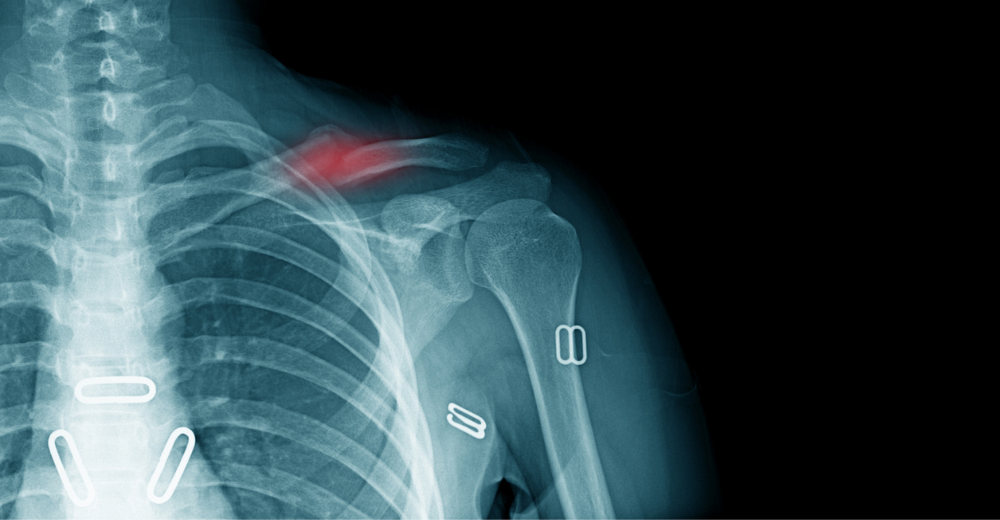

Questa radiografia è fondamentale per il corretto inquadramento diagnostico delle condizioni che coinvolgono la clavicola. L’Esame RX Clavicola è in grado di rilevare:

• Fratture e microfratture.

• Lussazioni o sublussazioni.

• Anomalie strutturali e deformità.

• Infezioni o processi infiammatori.

• Tumori ossei.

Questi dati consentono al medico di stabilire un piano terapeutico appropriato e di monitorare l’eventuale processo di guarigione.